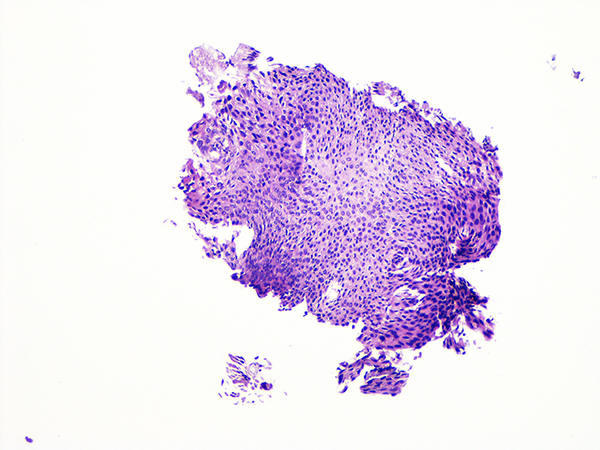

Case 4

Soft Bx CIN 3

40x - High Power |